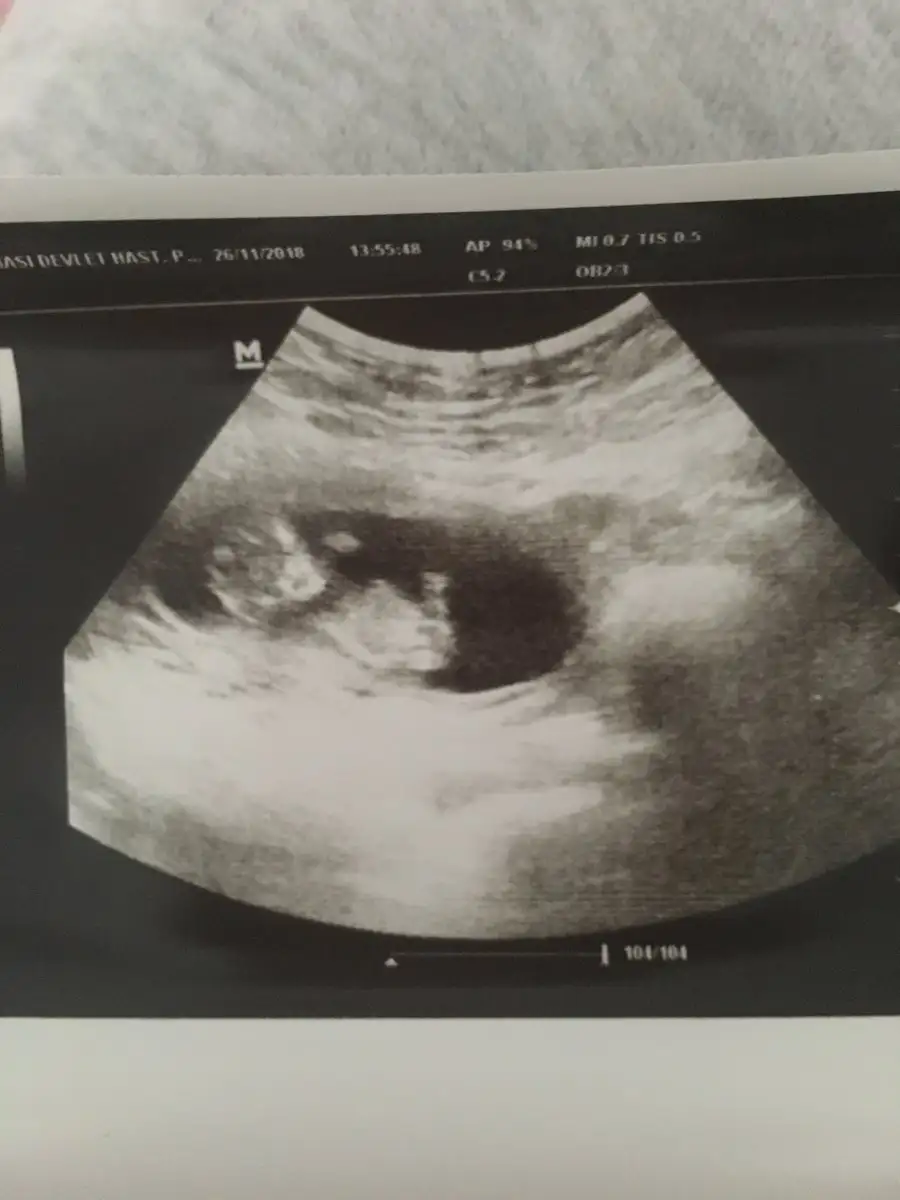

Maşallah bebişine inş lekelenme olmaz birdaha canım . Bidaha ki randevuda öğrenirsin cinsiyeti kesin olması daha iyi yüzde olarak bile söyleseler kesin değil ama heves yapıyoruz hemenBiz geldik kızlar bebiş gayet sağlıklı her şeyi iyi ilk defa kalp atışını dinledik sonunda çok şükür ikili test yatırmadım ama ense kalınlığı iyi dedi zaten %99 down sendromlu değil bebek dedi cinsiyeti ben gördüm çıkıntıyı ama doktor söylemedi erken diye sonra bidaha sordum çıkıntı var diye kızdı bu sefer önceliğin cinsiyet olmasın diye halbuki ben gördüm diye söyledim yani.. Çıkıntı yukarı bakıyordu ama doktorda çıkıntı var ama bidahakine söylerim yanılma payı var dedi onun dışında gece kahverengi leke gelmişti kese arkasında kanama var hafif dedi yat dinlen bol bol ilişki falan yasak dedi gripten çok öksürüyordum o zorlamış olabilir dedi öksürük için enfeksiyon hastalıklarına yolladı tahlil falan verdim gene bakalım kızlar bidaha leke gelirse gel dedi devamı gelmez inşallah :/ 1 hafta 2 günde gerideyiz gene Eki Görüntüle 2210124

Hiç hoş değil gerçekten seni öyle azarlar gibi konuşması! Ki sen lekelenme şikayetiyle gitmişsin senin moralini biraz düzeltmesi gerekirken bu yaptığı çok gereksiz. Bende çok ısrar ettim mecbur bir şeyler demek zorunda kaldı doktorum çok merak ediyorsun belli dedi anlattı uzun uzun kesin değil 1 ay sonra tam kesin olur ama çok meraklanırsan 2 hafta sonra gel yine bakarım dedi. Ama bebeğin iyiymiş ya gerisini boşver sen canım zaten kendin anlamışsın heralde :))Biz geldik kızlar bebiş gayet sağlıklı her şeyi iyi ilk defa kalp atışını dinledik sonunda çok şükür ikili test yatırmadım ama ense kalınlığı iyi dedi zaten %99 down sendromlu değil bebek dedi cinsiyeti ben gördüm çıkıntıyı ama doktor söylemedi erken diye sonra bidaha sordum çıkıntı var diye kızdı bu sefer önceliğin cinsiyet olmasın diye halbuki ben gördüm diye söyledim yani.. Çıkıntı yukarı bakıyordu ama doktorda çıkıntı var ama bidahakine söylerim yanılma payı var dedi onun dışında gece kahverengi leke gelmişti kese arkasında kanama var hafif dedi yat dinlen bol bol ilişki falan yasak dedi gripten çok öksürüyordum o zorlamış olabilir dedi öksürük için enfeksiyon hastalıklarına yolladı tahlil falan verdim gene bakalım kızlar bidaha leke gelirse gel dedi devamı gelmez inşallah :/ 1 hafta 2 günde gerideyiz gene Eki Görüntüle 2210124

Maşallah bebegine canım ne kadar büyümüş ufaklık darısı başımızaBiz geldik kızlar bebiş gayet sağlıklı her şeyi iyi ilk defa kalp atışını dinledik sonunda çok şükür ikili test yatırmadım ama ense kalınlığı iyi dedi zaten %99 down sendromlu değil bebek dedi cinsiyeti ben gördüm çıkıntıyı ama doktor söylemedi erken diye sonra bidaha sordum çıkıntı var diye kızdı bu sefer önceliğin cinsiyet olmasın diye halbuki ben gördüm diye söyledim yani.. Çıkıntı yukarı bakıyordu ama doktorda çıkıntı var ama bidahakine söylerim yanılma payı var dedi onun dışında gece kahverengi leke gelmişti kese arkasında kanama var hafif dedi yat dinlen bol bol ilişki falan yasak dedi gripten çok öksürüyordum o zorlamış olabilir dedi öksürük için enfeksiyon hastalıklarına yolladı tahlil falan verdim gene bakalım kızlar bidaha leke gelirse gel dedi devamı gelmez inşallah :/ 1 hafta 2 günde gerideyiz gene Eki Görüntüle 2210124

gözün aydın canım bebeğin sağlıklı olsunda. maşallah kuzuya. sen de çok dikkat et kendine inşallah olmaz artık leke vsBiz geldik kızlar bebiş gayet sağlıklı her şeyi iyi ilk defa kalp atışını dinledik sonunda çok şükür ikili test yatırmadım ama ense kalınlığı iyi dedi zaten %99 down sendromlu değil bebek dedi cinsiyeti ben gördüm çıkıntıyı ama doktor söylemedi erken diye sonra bidaha sordum çıkıntı var diye kızdı bu sefer önceliğin cinsiyet olmasın diye halbuki ben gördüm diye söyledim yani.. Çıkıntı yukarı bakıyordu ama doktorda çıkıntı var ama bidahakine söylerim yanılma payı var dedi onun dışında gece kahverengi leke gelmişti kese arkasında kanama var hafif dedi yat dinlen bol bol ilişki falan yasak dedi gripten çok öksürüyordum o zorlamış olabilir dedi öksürük için enfeksiyon hastalıklarına yolladı tahlil falan verdim gene bakalım kızlar bidaha leke gelirse gel dedi devamı gelmez inşallah :/ 1 hafta 2 günde gerideyiz gene Eki Görüntüle 2210124